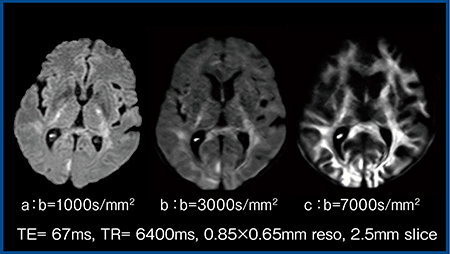

1.b値の影響

TR,TEは固定でb値を1000,3000,7000s/mm2と変化させた画像を示す(図2)。b値の上昇に伴い皮質の信号が徐々に低下するため,本症例の場合はb=3000s/mm2(図2 b)が最も病変が明瞭である。通常b=7000s/mm2(図2 c)という高b値で撮像するとTEが延長しSNRが低下してしまうが,ZGOではTE=67msで撮像可能で非常に良好な画像が得られるので驚きである。

図2 DWIにおけるb値の影響